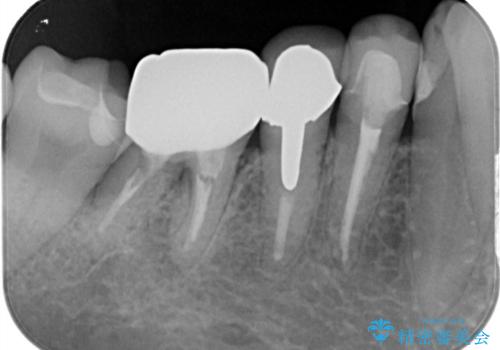

- フロスをしていたが歯と歯の間にはさまり、取れなくなったとのご相談にいらした患者様です。以前、他院で治療した部分に凹みがあり、その部分にフロスが残留しちぎれていました。このため、根本的に歯のかぶせ物・詰め物を新しくする必要があると判断いたしました。治療後はフロスでのケアもスムーズになり、良好な経過をたどっています。

一般的に、失活歯(根の治療をし、神経を取り除いてある歯)はそうでない歯と比較し、噛み合わせの力がかかりやすいといわれています。残存する歯質の量にもよりますが、歯の破折を防ぐためにクラウン(かぶせ物)を選択するケースが多いです。